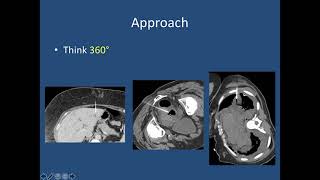

Image Guided Percutaneous Drainage of Abnormal Abscesses and Fluid video

Image-Guided Percutaneous Drainage of Abnormal Abscesses and Fluid

Image-Guided Percutaneous Drainage of Abnormal Abscesses and Fluid Image-Guided Percutaneous Drainage of Abdominal Abscessed and Fluid Collections

Image-Guided Percutaneous Drainage of Abnormal Abscesses and Fluid

Image-Guided Percutaneous Drainage of Abnormal Abscesses and Fluid Image-Guided Percutaneous Drainage of Abdominal Abscessed and Fluid Collections